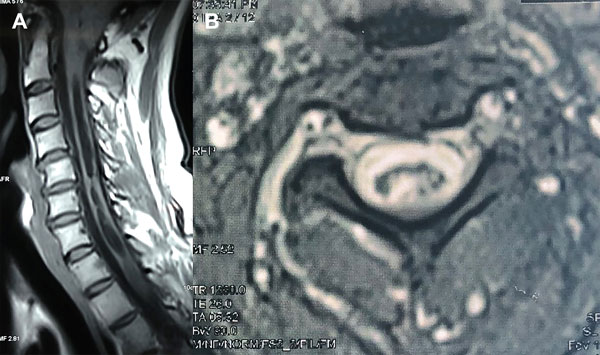

Estas secuencias permiten una evaluación cualitativa con valoración subjetiva del pasaje del LCR a través de las cisternas (Figura 1) y una valoración cuantitativa de la velocidad (Figura 2). La adquisición de las mismas se realiza de forma coordinada con el latido cardíaco (gatillado mediante el censado por el electrocardiograma o curva de pulso).13

Figura 1: Evaluación cualitativa en RM con técnica de contraste de fase. A: Imagen ponderada en T2 de alta resolución de cortes finos (3mm) que muestra el descenso amigdalino a través del foramen magno, el compromiso de las cisternas peritroncales y una siringomielia con imagen de turbulencia de flujo en su interior. B: Imagen en secuencia de fase que utiliza el contraste entre negro y blanco mostrando con señal hiperintensa el flujo de LCR cisternal C: Imagen de magnitud en fase anterógrada que muestra con señal hiperintensa el flujo en sístole. D: Imagen de magnitud en fase retrógrada que muestra con señal hipointensa el flujo en diástole. Con la valoración de estas secuencias en su totalidad y en reproducción en cine de las imágenes estáticas se logra la evaluación del pasaje de LCR a través de las cisternas peritroncales y los forámenes del cuarto ventrículo.

Figura 5: Caso 3. A: RM de columna cervical en plano sagital ponderada en T1, postoperatoria que muestra una siringomielia con ocupación parcial del canal. B: RM de columna cervical en plano axial ponderada en T2 postoperatoria que sugiere una comunicación entre la cavidad siringomiélica y el espacio subaracnoideo.